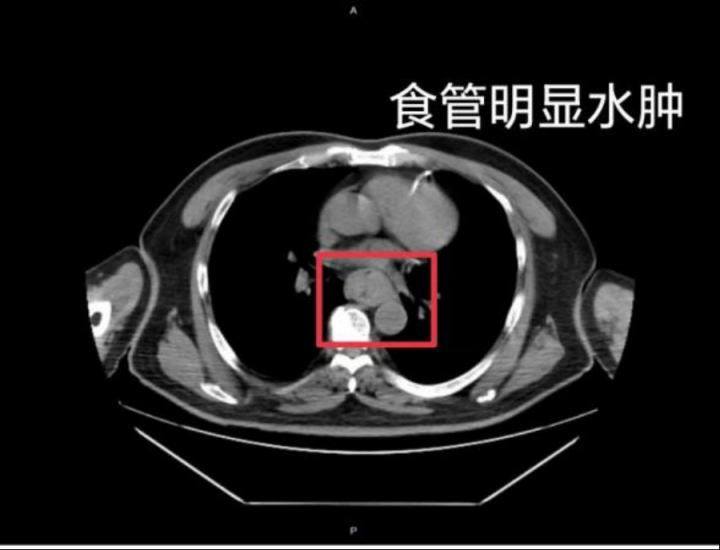

据网友回忆,“自己去厕所尝试呕吐时,直接呕出了血,一大口鲜血从嘴里喷出,总共吐了两次。”CT结果显示,他的食管全部水肿损伤。